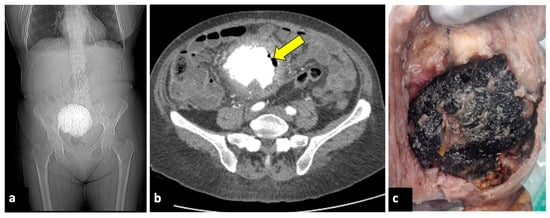

Infection of leiomyomas (pyomyoma) is an infrequent complication of uterine fibroid but is associated with high morbidity and mortality. It may occur in postmenopausal women, during pregnancy, in the postpartum period, or as a complication of uterine artery embolisation for treating leiomyomas [52,53]. Its clinical symptoms usually include fever and PAA. The diagnosis of pyomyoma is tricky because of its insidious presentation and lack of reported imaging and clinically typical findings. However, the presence of air within the myoma at CT evaluation is a crucial finding when there is a suspected infection (Figure 8). MRI may reveal a uterine mass with an inhomogeneous central hyperintensity component, suggesting the presence of blood products, necrotic tissue, and purulent fluids. Air components within the lesion show low signal intensity on T1, T2, and DWI [54].

Figure 8.

Pyomyoma in an eighty-year-old woman with a history of diabetes and steroid treatments who presented at the emergency department with fever, leucocytosis, and abdominal cramps for a week. A previous X-ray (a) shows a calcific uterine myoma. Axial CT scan (b) demonstrated the presence of air within the myoma (yellow arrow), eliciting the suspicion of an infected myoma. The patient underwent a hysterectomy (c), and the pathological findings confirmed the diagnosis of pyomyoma.